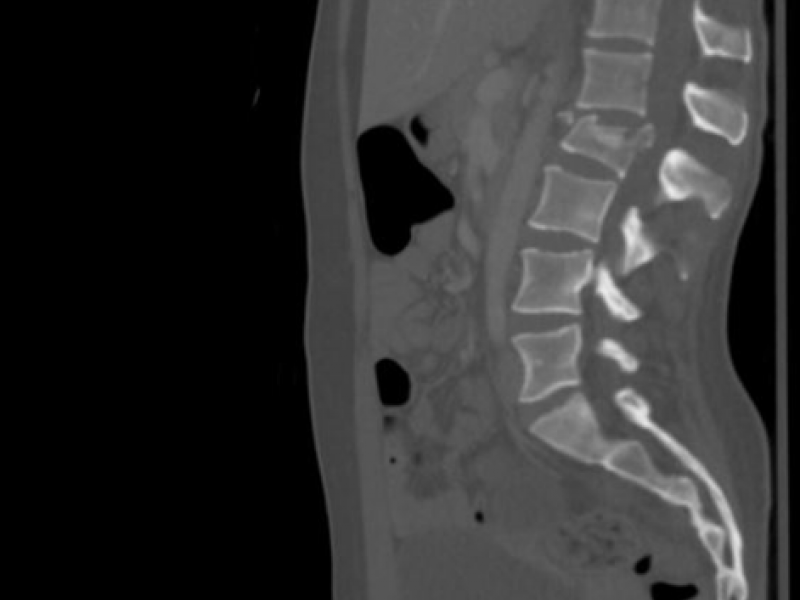

A trauma alert is called for a 20-year-old male involved in